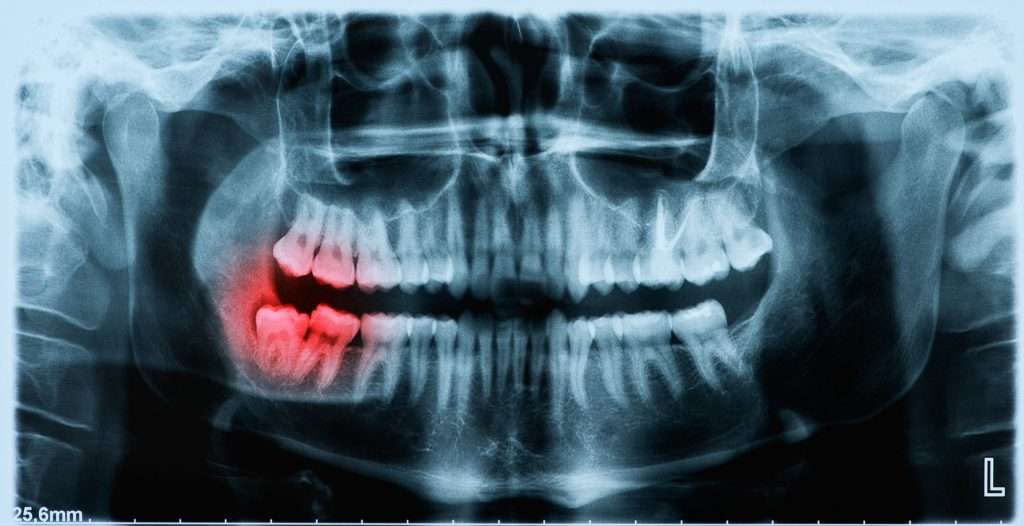

Wisdom Teeth in Adulthood: Why Age Matters

Wisdom Teeth in Adulthood: Why Age Matters The management of third molars, commonly referred to as wisdom teeth, is a frequent topic of discussion in dental health. While often associated with late adolescence, the extraction of wisdom teeth is a procedure frequently performed on adults of varying ages. Memorial Oral & Maxillofacial Surgery emphasizes the […]

Wisdom Teeth and Orthodontics: Does removing third molars actually prevent your teeth from shifting?

Wisdom Teeth and Orthodontics: Does Removing Third Molars Prevent Dental Shifting? For decades, a common concern among dental patients and parents of teenagers has been the potential for wisdom teeth to disrupt orthodontic work. After investing significant time and resources into braces or aligners to achieve a perfectly aligned smile, the fear that erupting third […]